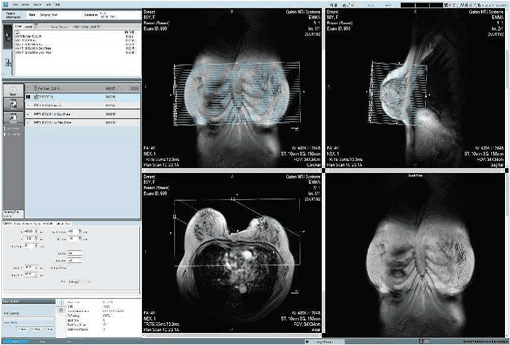

Intelligent Software & AI-Driven Imaging

PRODIVA Software Platform

EMMA is powered by PRODIVA, an intelligent MRI software platform developed in-house by Time Medical. It enhances the entire imaging workflow—from scan planning to image review.

Key Benefits of PRODIVA:

- Automated scan planning

- Intuitive graphical user interface

- Clinically optimised pulse sequences

- Consistent image quality across examinations